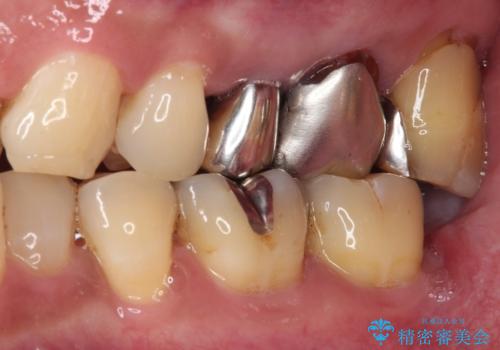

抜歯が必要な小臼歯 インプラントによる補綴治療

- 頻繁に銀歯が外れてしまうとのことで来院された患者様です。

歯肉の中、深いところまでむし歯が進行しており、歯根を部分矯正で引っ張り出してから補綴治療を行うか、抜歯してインプラント補綴治療を行うか選択することになりました。

ジルコニアカスタムアバットメントは、歯肉ラインに金属が見えにくいというだけでなく、クラウンを装着する土台の形が天然歯と近い形態となるため、清掃性が高く歯肉が腫れにくいというメリットがあります。

インプラントは、骨との生着能が比較的高いとさせるSLAタイプを使用しました。